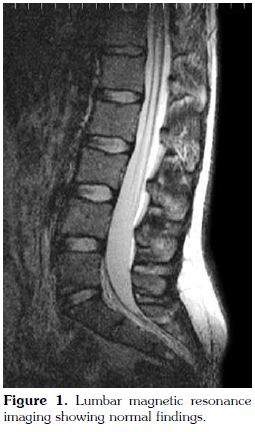

There were no abnormal findings of the lumbar spine on magnetic resonance imaging (MRI) (Figure 1). Contrast enhanced sacroiliac MRI revealed lobulated, multivesicular cystic lesions, which originated from the second sacral vertebra, extending to the sacral ala and iliac wing at the third sacral level, which also filled the sacroiliac joint. Vesicular lesions in the sacroiliac joint and piriform muscles showed increased contrast uptake (Figure 2). Given the patient's medical history, bone hydatid disease and other cystic bone lesions were included in differential diagnosis.